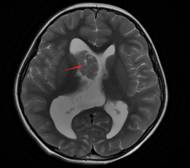

3T薄层(层厚<1mm)扫描的头颅MRI联合特殊序列(如FLAIR、SWI、QSM)可识别微小病变。例如,FCD II型在MRI上可能表现为“皮质增厚-白质信号异常-灰白质分界模糊”三联征。

图中红色圆圈内显示右侧前颞FCD病变